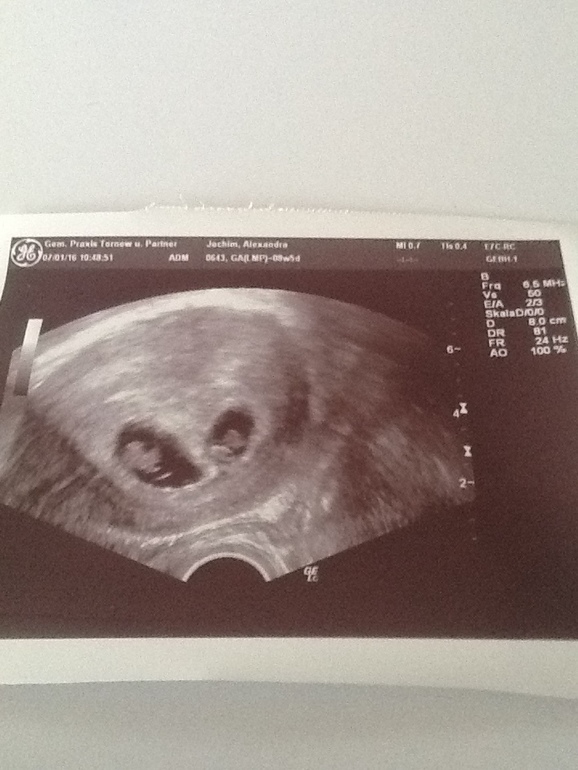

Сходила я на узи сегодня у нас 38 дпп. . Напомню что на 22 дпп увидели 1 плодное яйцо, а сегодня тааадааамммм и нас там двое !!!

Видела как пульсируют два сердечка!!! Это не передаваемые ощущения. Поплакала от счастья прям на кресле ! Они такие маленькие , но такие хорошенькие !!! Такие родные и любимые и долгожданные !!!